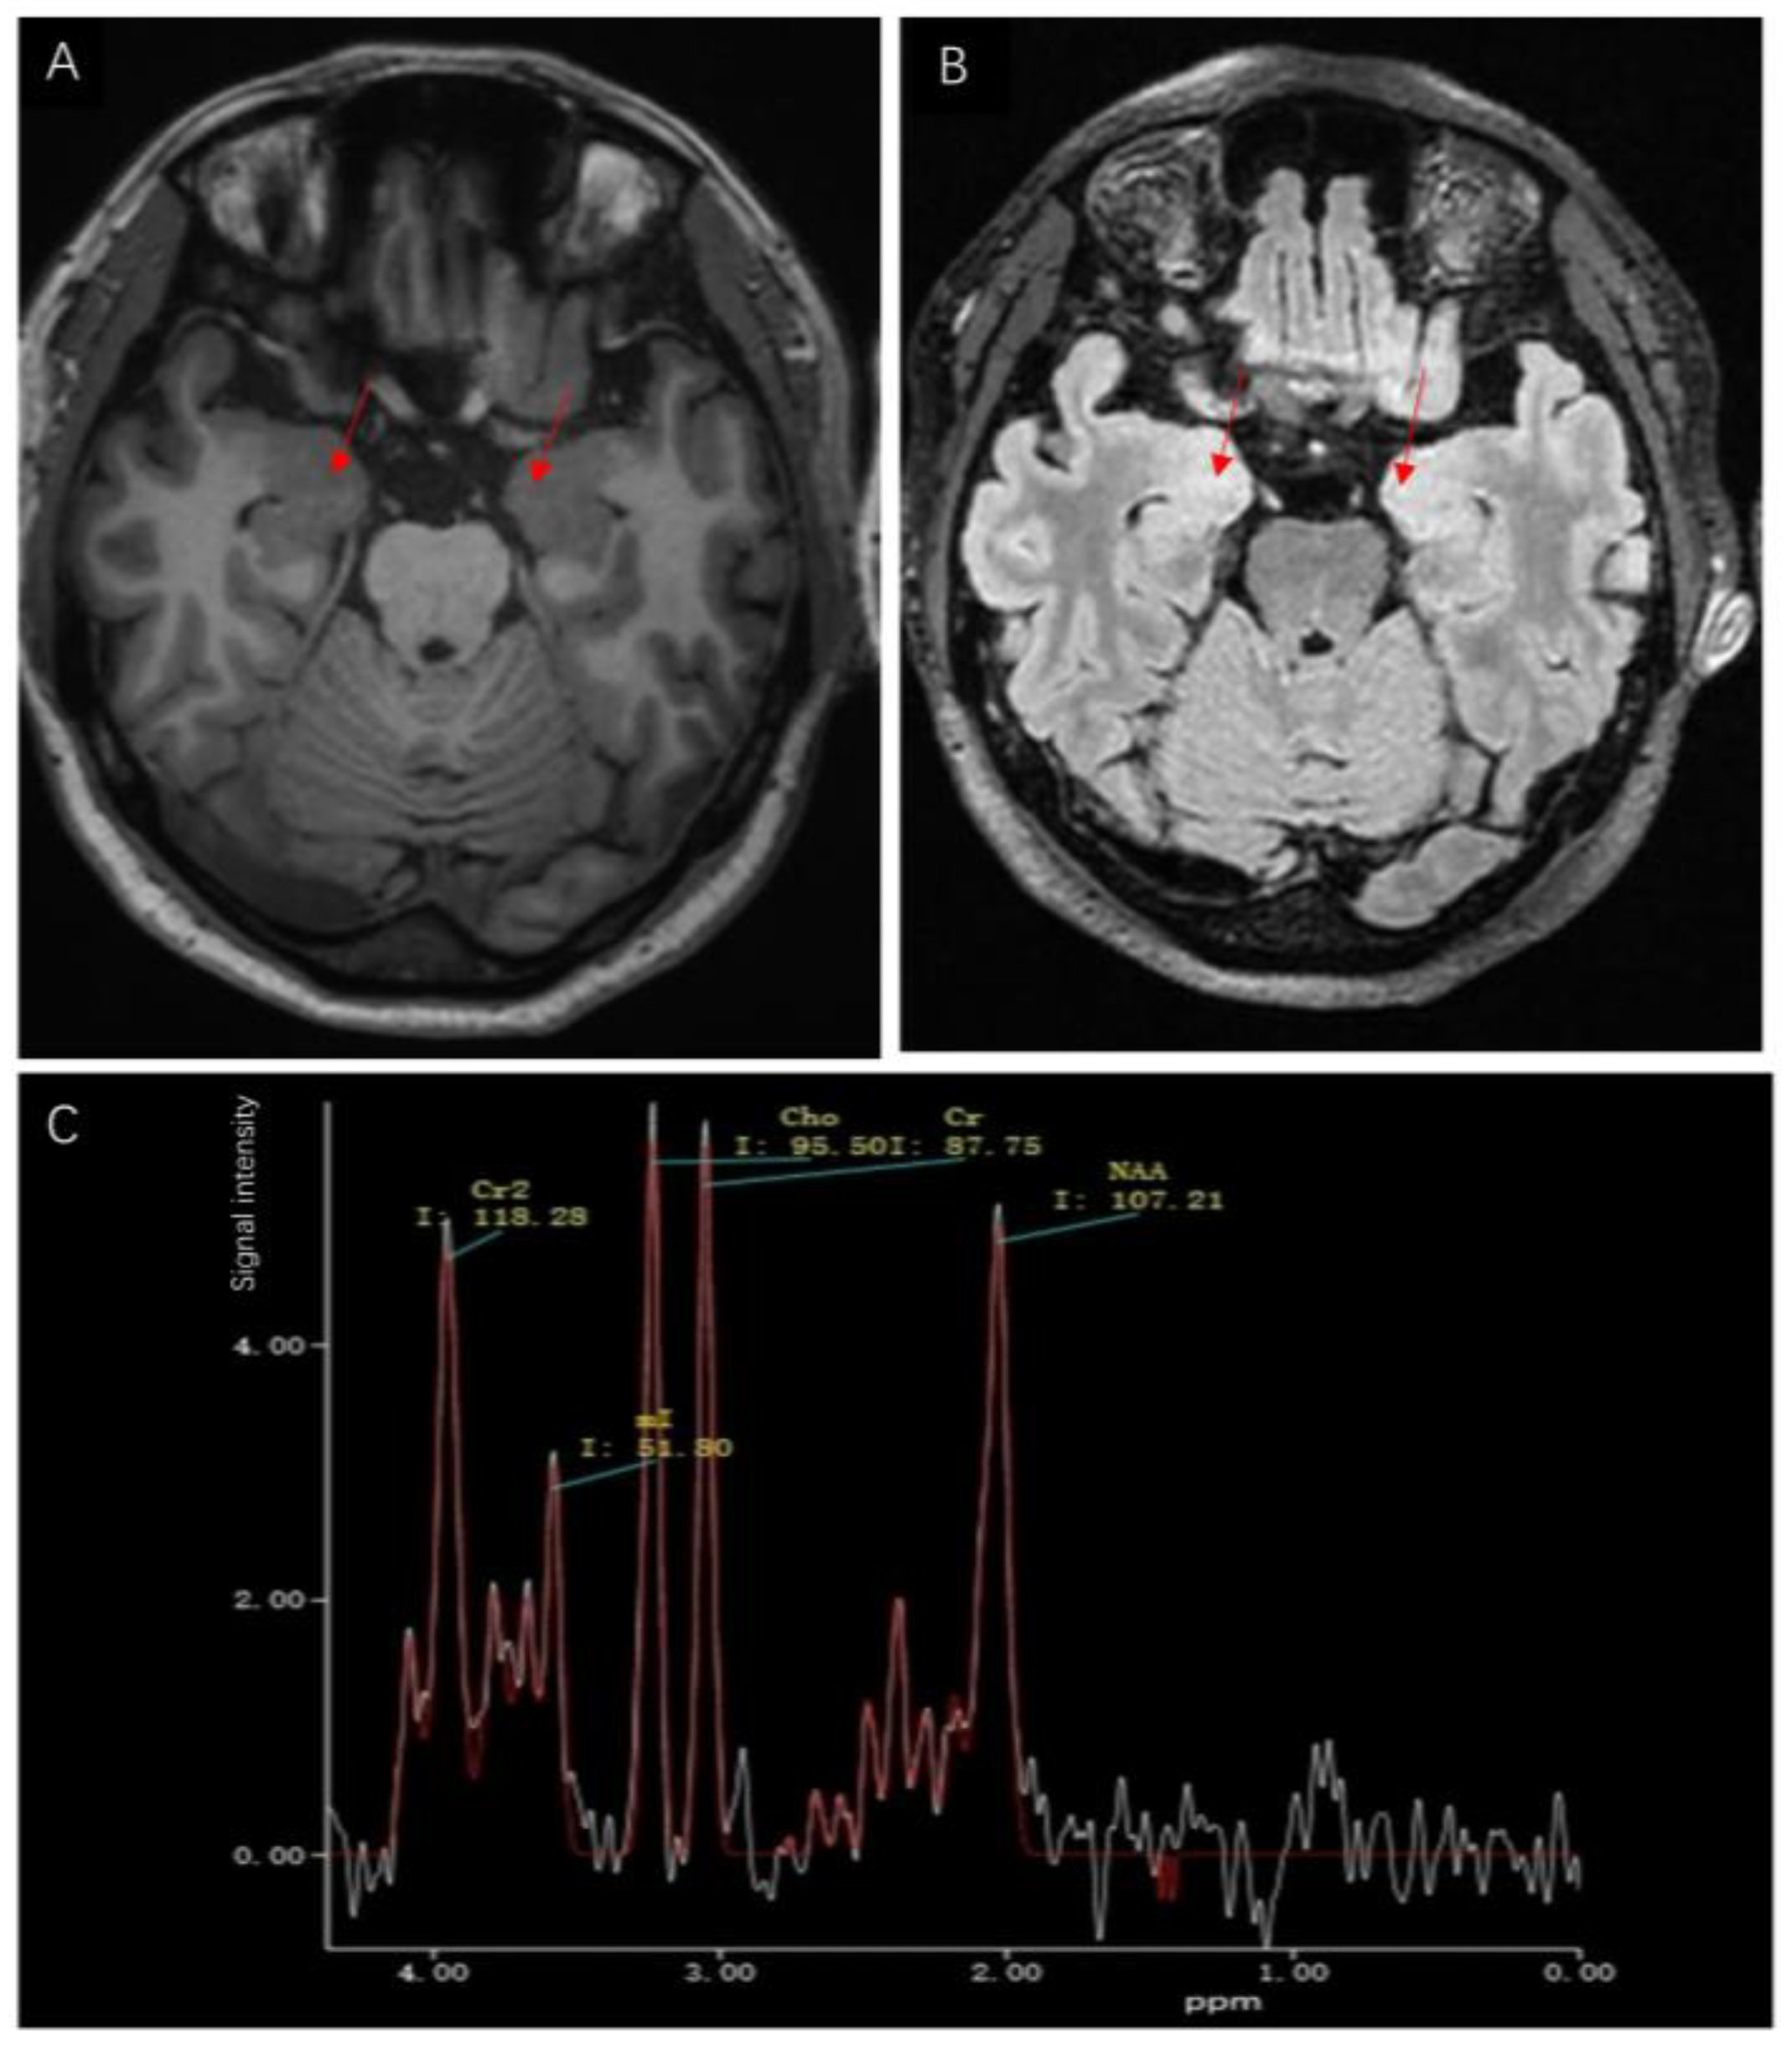

The etiology of the seizures and limb stiffness remains unknown. Because the Babinski sign was present on the right, cerebrovascular disease could not be excluded, so magnetic resonance imaging (MRI) was performed. A few white matter lesions were seen, and the spectrum of the bilateral temporal lobe hippocampus showed a decreased NAA/Cho + Cr ratio in the left hippocampus (Figure 1A–C). According to the Magnetic resonance spectroscopy, the neurons in the left hippocampus might be damaged or denatured. The Electroencephalogram (EEG) was abnormal with several atypical sharp-slow wave complexes of medium and high amplitudes in the bilateral frontal and temporal areas during awake and sleep, especially in the right frontal area. Temporal lobe epilepsy was considered based on the results of the EEG and magnetic resonance spectroscopy. Considering that encephalitis also causes an increase in the frequency of epilepsy, the patient underwent lumbar puncture on the second day of hospitalization. The cerebrospinal fluid (CSF) was colorless and transparent, with a pressure of 70 mm H2O, which is slightly lower than normal. The white blood cell count in CSF was normal. Gram staining of the CSF was negative for Gram-positive and Gram-negative bacteria and India ink staining was negative for Cryptococcus. Cerebrospinal fluid protein, glucose, and chloride levels were 289.0 mg/L, 3.63 mmol/L, and 129.8 mmol/L, respectively. No obvious abnormality was found on routine biochemical examinations of the CSF; however, the anti-GAD65 antibody was found to be positive in the antibody panel for autoimmune encephalitis using indirect immunofluorescence assay of the serum and CSF (Figure 2A,B). The anti-GAD65 antibody titers were both 1:100, and the remaining antibodies were negative. Given that the patient had repeated seizures with a loss of consciousness and poor treatment effect of antiepileptic drugs, the patient was diagnosed with autoimmune encephalitis with anti-GAD65 antibody and her epileptic symptoms were secondary to autoimmune encephalitis. Since anti-GAD 65 autoimmune encephalitis may be associated with tumors, the patient underwent computed tomography (CT) of the lungs and abdomen and a breast B-ultrasound. The tumor marker C12 was also tested. Fortunately, no tumor was found.

Figure 1.

(A) Axial T1 weighted magnetic resonance images of the hippocampus showed no significant abnormalities in the bilateral hippocampus (red arrow). (B) Axial fluid-attenuated inversion recovery (FLAIR) showed no significant abnormalities in the bilateral hippocampus (red arrow). (C) Magnetic resonance spectroscopy image showed a decreased NAA/Cho + Cr ratio (1.22/(1.09 + 1.00) = 0.58) in the left hippocampus.